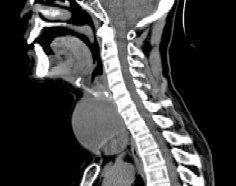

入院后的检查结果让医生皱起眉头,肿瘤直径达到7.4cm,充斥着整个脖前,并与颈部重要血管、神经紧密粘连,更棘手的是,部分瘤体已坠入胸骨后。在这种情况下手术,稍有不慎,就可能损伤喉返神经导致永久性声音嘶哑,或损伤甲状旁腺导致终身手足抽搐。